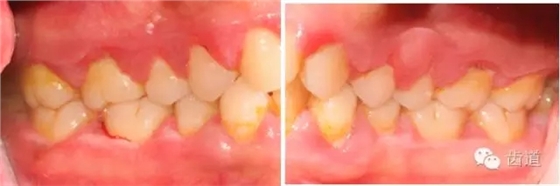

1、口腔衛(wèi)生狀況及局部刺激物(牙菌斑、牙石,不良修復體)

牙石及不良修復體

2、牙齦

(顏色、形狀、質地、退縮、BOP、PD、附著齦)